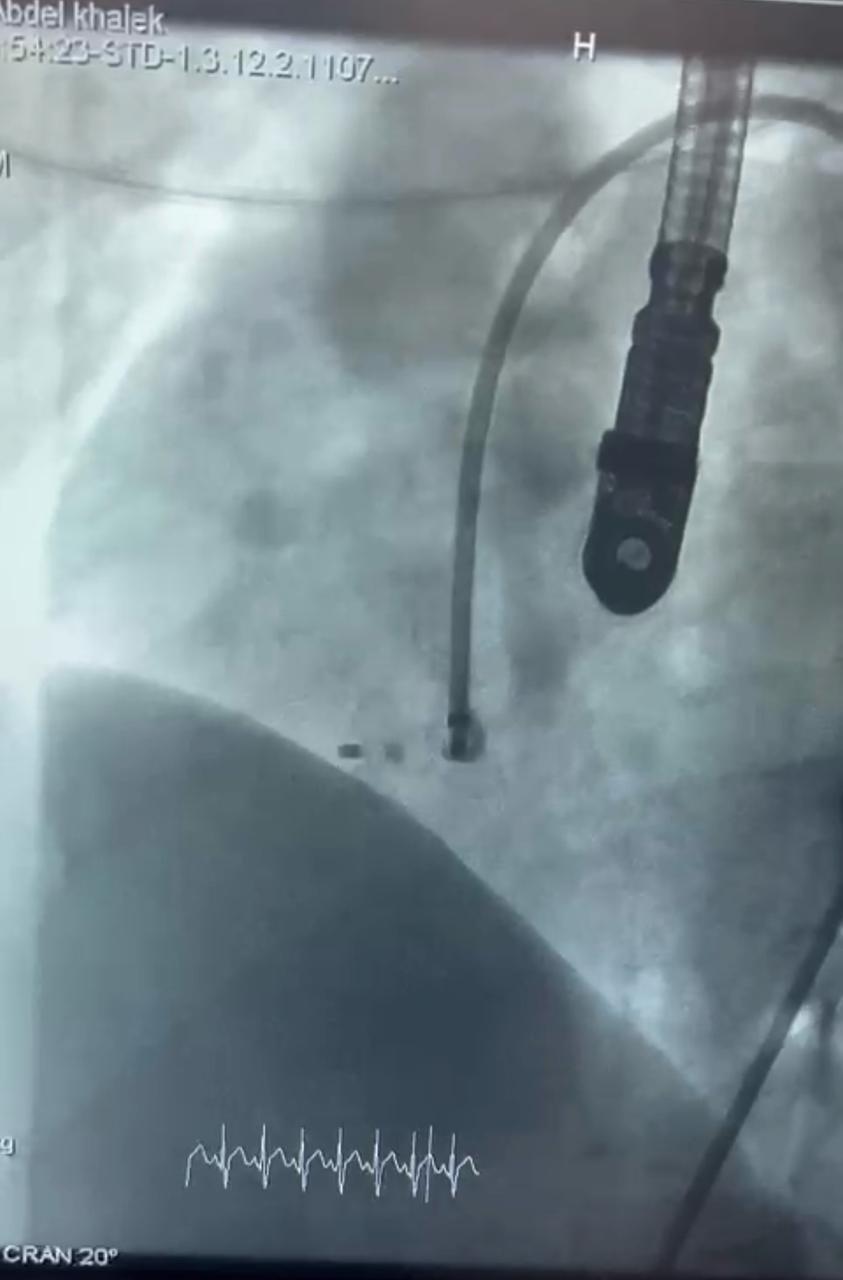

نجح الفريق الطبي بوحدة قسطرة الأطفال جامعة سوهاج، في إجراء ثلاث عمليات دقيقة ومعقدة بالقسطرة التداخلية لأطفال تتراوح أعمارهم بين ٣ و١٣ عامًا، في إنجاز طبي جديد يُضاف إلى سجل مستشفى سوهاج الجامعي، وذلك خلال يوم واحد فقط، باستخدام أحدث الأجهزة والتقنيات.

وقال الدكتور مجدي القاضي، عميد كلية الطب البشري ورئيس مجلس إدارة المستشفيات الجامعية جامعة سوهاج، بأن العمليات الثلاث تمثل نقلة نوعية في علاج العيوب الخلقية بالقلب لدى الأطفال، حيث تمت بإستخدام القسطرة التداخلية دون الحاجة إلى تدخل جراحي مفتوح، مما يُسهم في تقليل المضاعفات وتسريع معدلات الشفاء.

وأوضح الدكتور أحمد كمال عبدالحميد، المدير التنفيذي للمستشفيات الجامعية جامعة سوهاج، أنه تم علاج الطفلة حور (٣ سنوات) والتي كانت تعاني من ثقب بين الأذنين، وتم غلقه بإستخدام جهاز أمبلاتزر، والطفلة مريم علي (٦سنوات) التي كانت تعاني من ثقب بين الأذنين مصحوب بتضخم في القلب ونقص في النمو، وتم علاجها بإستخدام جهاز لايف تك، والطفلة فاطمة (١٣ سنة)، والتي كانت تعاني من ثقب بين البطينين، وتم إغلاقه بإستخدام جهاز كونار لايف تك، وهو من أحدث أجهزة إغلاق الثقوب عالميًا.